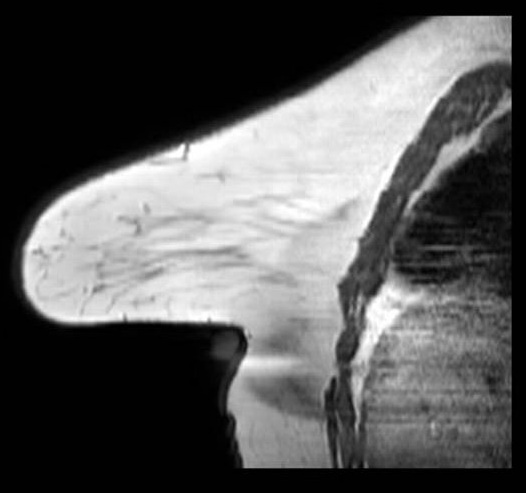

Chemical Shift

Chemical shift artifact on localizer image. Sagittal localizer image demonstrates prominent dark and bright bands at fat-water interfaces at the anterior and posterior breast margins. Localizer sequences are typically acquired with limited receiver bandwidth, which increases the frequency-encode pixel shift between fat and water and renders chemical shift artifact more conspicuous than on diagnostic sequences. The spatial offset is proportional to field strength and inversely proportional to bandwidth.